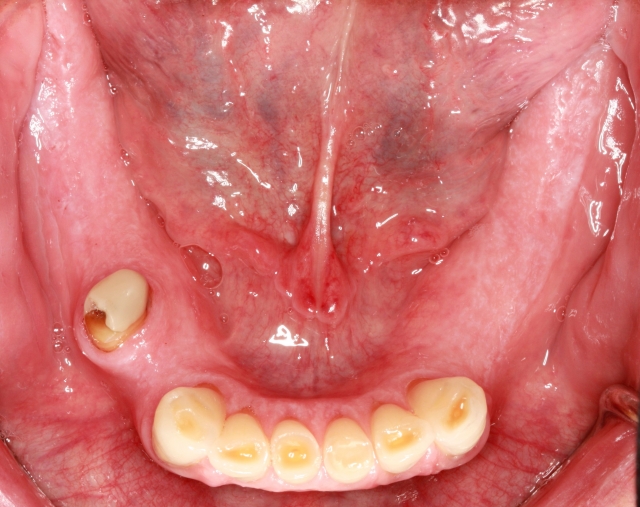

- The opposing occlusal contacting surfaces can also contribute to the patient’s ability to tolerate the palatal coverage of a maxillary removable denture. A patient who has full stabilizing contact with lower teeth is very different than a patient with an upper denture opposing lower teeth in the canine-to-canine area. Imagine the challenge to the seal of an upper removable denture when the only functional opposing contact is in the anterior segment, as would be the case with Fig. 4. When the denture comes loose in the posterior segment, a cycle is created where the protective reflex is initiated by the contact with the posterior third of the tongue brushing against the posterior denture base that has dropped down. In a contrasting thought, it might be interesting to investigate sleep apnea for a patient curiously devoid of a trigger to the gag reflex.